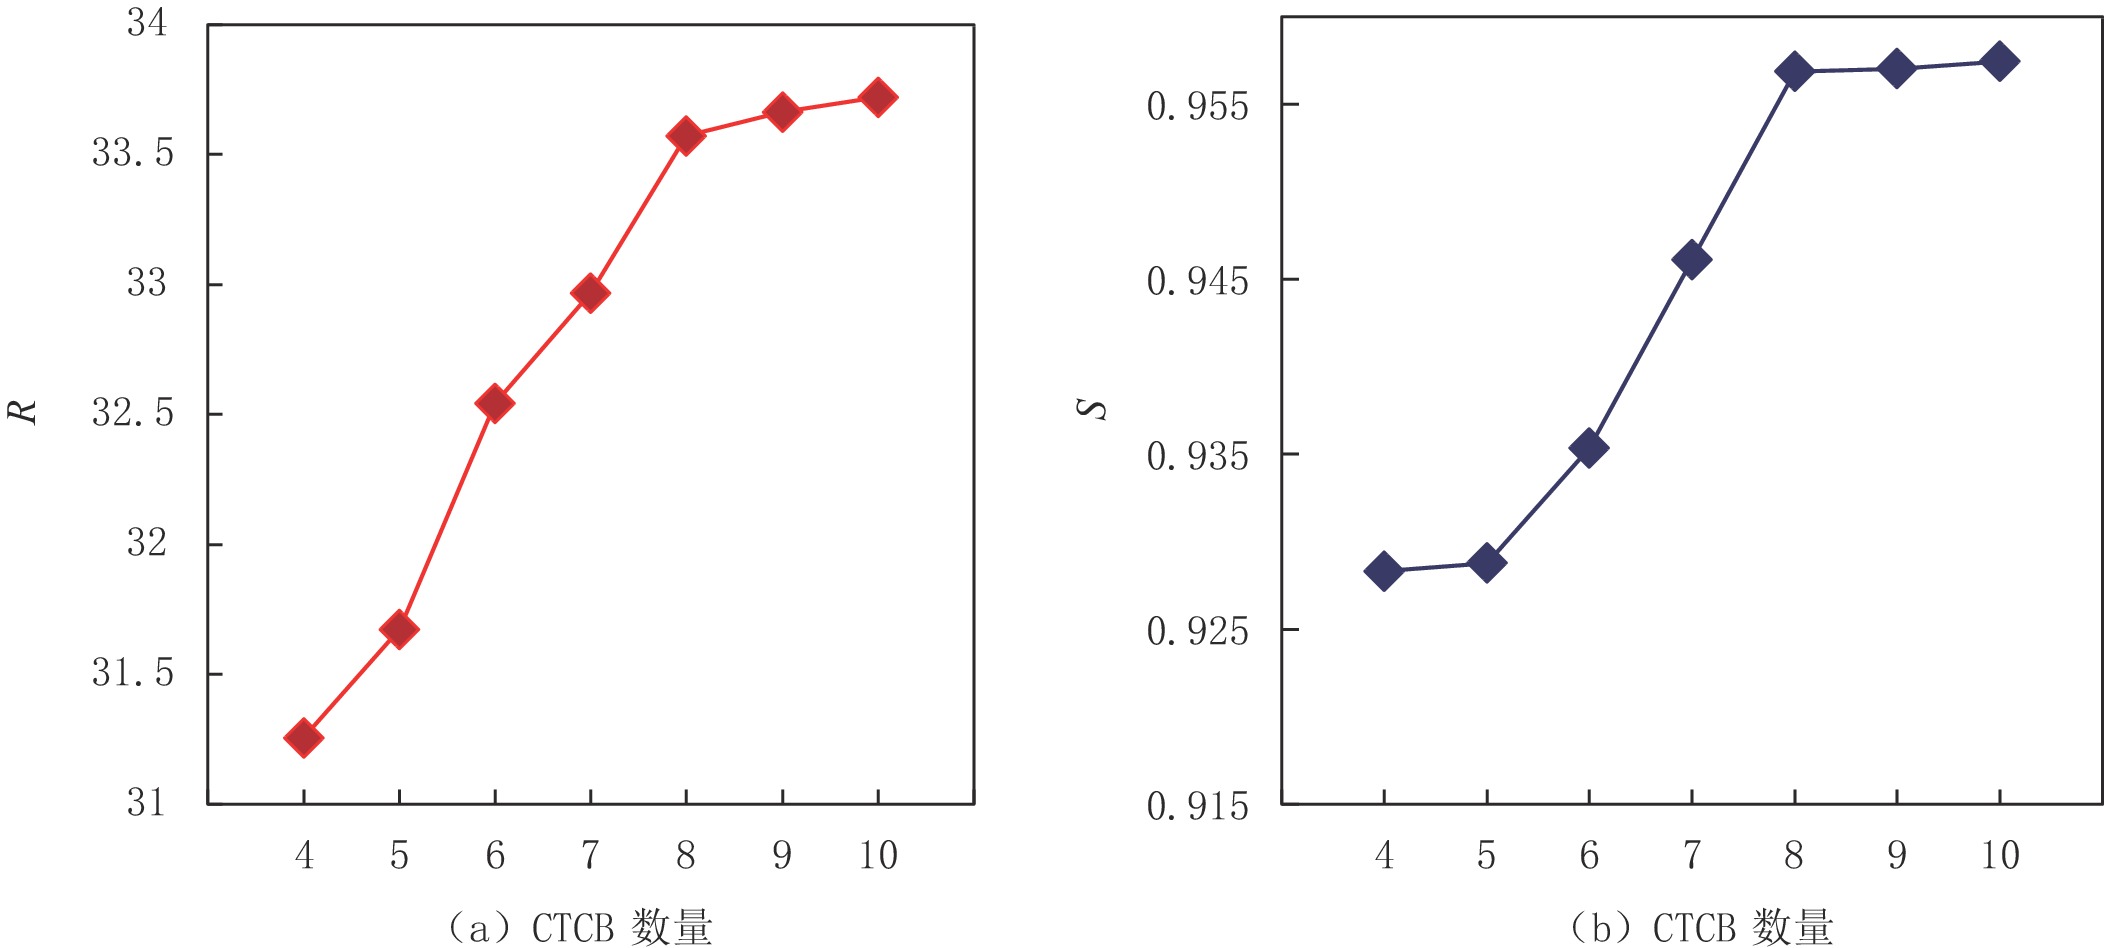

在其他参数一致的情况下,使用峰值信噪比和结构相似度两项客观指标评估CNN和Transformer耦合模块(CTCB)的数量对网络结构的影响。不同CTCB数量下R和S值的折线图如图8(a)和图如图8(b)所示。从中可以看出,网络性能与CTCB数量成正比,且随着层数的增多,网络性能逐渐达到饱和。综合考虑网络复杂性、网络性能与训练时长等因素,我们将该网络的CTCB数量设置为8。